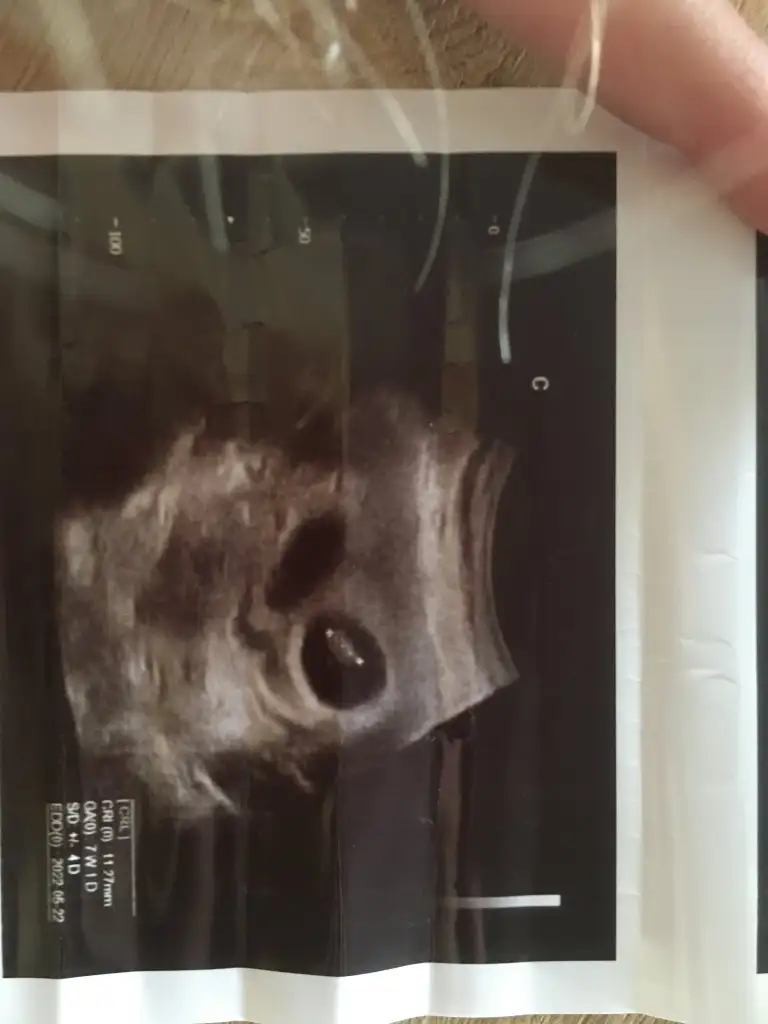

Fatoş canım buna bakar mısın ,elinde ki ultrasyon kağıdıyla karşılaştırır mısın merak ettimGeçen hafta kaşıntı ve akıntı için gittiğimde mantar için fitil ve merhem vermişti doktorum. Kaşıntım geçti ama akıntı devam ediyordu bugün tekrar gittim ve doktor akıntı kültürü aldı tahlile gönderdi bakalım sonuç 5 gün sonra filan çıkıcak. Aynı sıkıntıları yaşayanlar vardı onlar için yazayım dedim. Bugün 12+0 ız ve cinsiyeti tam göremiyorum ama erkeğe benziyor çıkıntı gördüm sanki dedi2 oğlandan son 3.oğlan geliyor galiba. Neyse üzülmiycem rabbim sağlıkla versin de gerisi başımın üstüne.

Kız senin için gittim buldum ilk haftalardaki ultrason kağıdını valla kağıda göre solda duruyo. O zaman erkek oluyo galiba yazıya göre. Yok anacım nerden bakarsam bakayım kız ihtimalini bulamıyomFatoş canım buna bakar mısın ,elinde ki ultrasyon kağıdıyla karşılaştırır mısın merak ettim

Bu fotoğrafa göre benimki erkek oluyorFatoş canım buna bakar mısın ,elinde ki ultrasyon kağıdıyla karşılaştırır mısın merak ettim